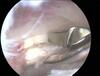

Arthroscopic image of a knee shows the posterior cruciate ligament bundle origins. The anterolateral bundle (ALB) and the posteromedial bundle (PMB) are observed at their origin on the lateral side of the medial femoral condyle (MFC), or the medial intercondylar notch.

• primary restraint to posterior tibial translation, greatest instability at 90 of flexion.

• AL tight in flexion, strongest/most important for stability at 90 “PAL” PCL

• PM tight in extension.